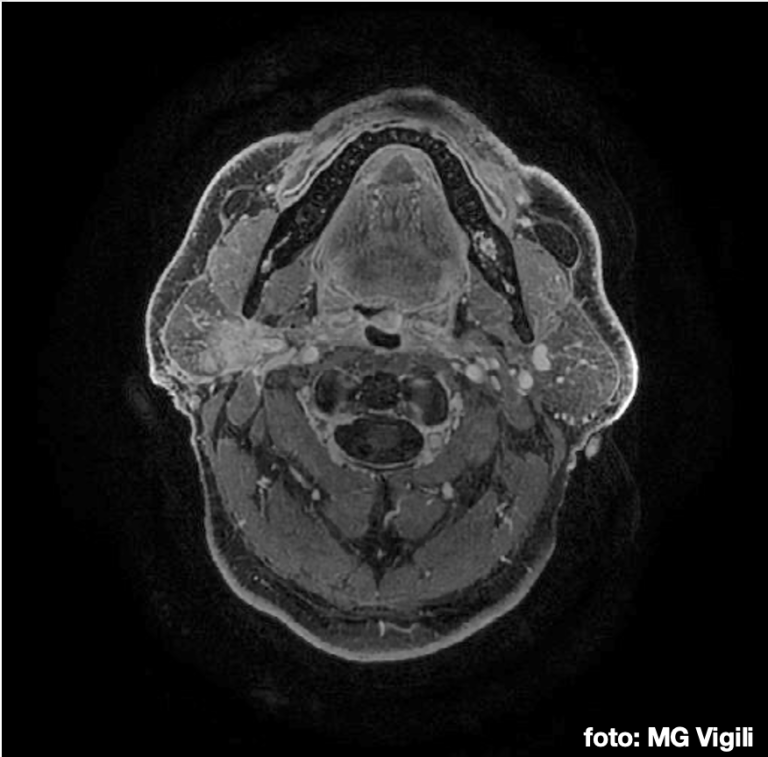

Effetti tardivi e tossicità nei sopravvissuti ai trattamenti per tumori maligni delle ghiandole salivari maggiori